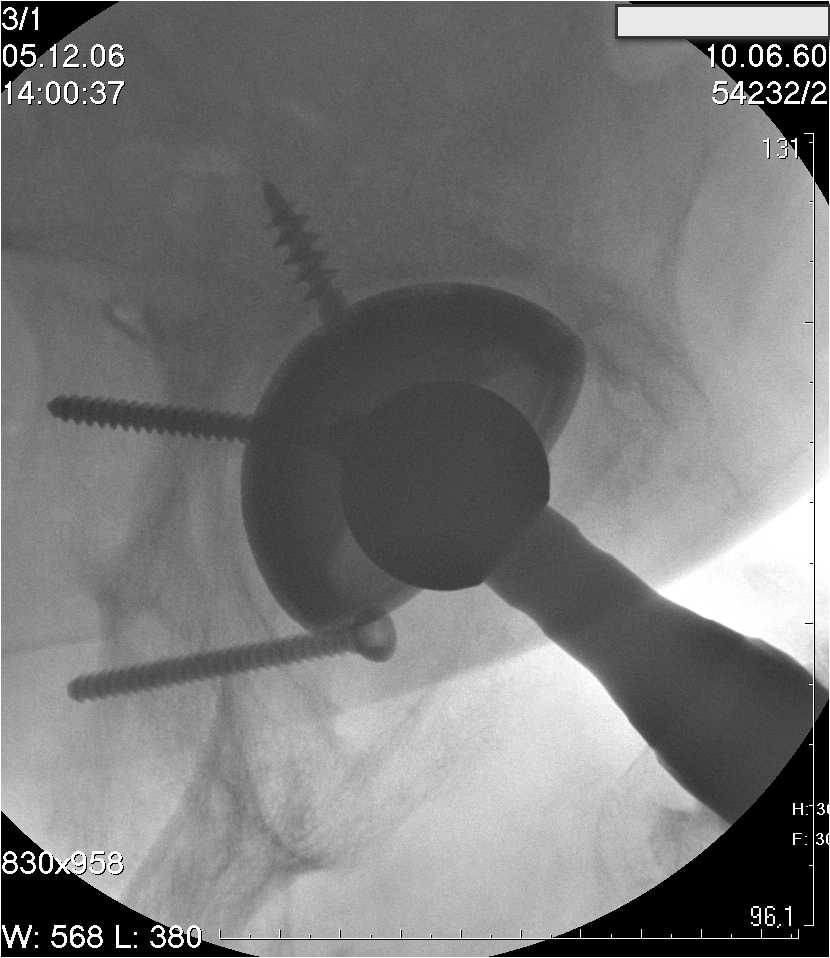

Уважаемые коллеги.В 3 Центральный Военный Клинический Госпиталь имени А. А. Вишневского, что в Красногорске, Московской области, в отделение эндопротезирования крупных суставов поступил пациент 1960 года рождения Жалобы при поступлении: на боли в области левого тазобедренного сустава (больной указывает на точку расположенная в середине условной линии между седалищным бугром и большим вертелом), усиливающиеся в начале ходьбы, при опоре на левую ногу с иррадиацией болей по наружной и наружно-задней поверхности левого бедра, левый коленный сустав; снижение объема движения в левом тазобедренном суставе, снижение опорной способности левой нижней конечности, хромоту на левую ногу, необходимость использования дополнительной опоры (костыли) при ходьбе, снижение объема двигательной активности из за болей в суставе.В анамнезе: Со слов больного, согласно медицинских документов, в 1989 году получил травму левой нижней конечности: закрытый перелом левой вертлужной впадины с центральным вывихом головки левой бедренной кости. Лечился консервативное. В процессе лечения сформировался посттравматический артроз, укорочение левой нижней конечности до 5 см. 25.04.2005 года в Подольском Окружном Госпитале Министерства Обороны выполнено: одномоменто, остеосинтез заднего края вертлужной впадины фрагментом резецированной головки бедренной кости и тотальное эндопротезирование левого тазобедренного сустава бесцементным эндопротезом "VERSIS ET" с бесцементной чашкой TRILOGY. Послеоперационный период осложнился ранним нагноением области эндопротеза, в результате санаций очага инфекции и антибиотикотерапии, активного промывного дренирования антисептиками, послеоперационная рана зажила. После операции, со слов больного, через два месяца в полном объеме стал нагружать левую нижнюю конечность. В течение полгода, после операции чувствовал себя вполне удовлетворительно. С марта 2006года стал отмечать появление болей в области тазобедренного сустава, то в области паха, то в области левой ягодицы. С августа месяца отмечает те жалобы, с которыми он сейчас к нам обратился. Температура тела, после заживления раны, нормальная. В анализах крови, лейкоциты около 7 тыс, формула нормальная, СОЭ 12 мм ч. Локально: при осмотре обеих нижних конечностей, анатомическая ось конечности не нарушена; отмечено относительное укорочение левой н\конечности на 1.5 см., гипотрофия мышц левого бедра 3 см, голени 2 см, симптом. Объем движений в тазобедренных суставах: правый~ сгибание- 60 гр, разгибание-180 гр ,отведение- 35 гр, левый~ сгибание- 110 гр , разгибание-170 гр , отведение-15 гр. Контуры других суставов н/конечностей обычные, объем движений в них не страдает. Пульсация на артериях конечностей удовлетворительная. Неврологические нарушения конечностей отсутствуют, рефлексы на обеих н/конечностях одинаковые, чувствительных нарушений нет. Осевая нагрузка на левую нижнюю конечность вызывает боль в точке расположенная в середине условной линии между седалищным бугром и большим вертелом. Отмечается пигментация и пастозность нижней трети обеих голеней и стоп, характерная для посттромботической болезни. На Цветном дуплексном сканировании сосудов нижних конечностей: Нестенозирующий атеросклероз обеих бедренных и подколенных артерий . Гемодинамически значимых препятствий кровотоку в магистральных артериях ног не выявлено. Глубокие и поверхностные вены нижних конечностей проходимы. Умеренная недостаточность клапанов подколенных вен. Данных за тромбоз глубоких вен на момент осмотра не получено.А вот что пишет наш рентгенолог: На серии рентгенограмм области левого тазобедренного сустава определяется тотальный бесцементный эндопротез. Вокруг тени чашки эндопротеза определяется ободок остеорезорбции. Кроме того, визуализируется деформированный костный винт фиксирующий консолидированный отломок вертлужной впадины, вплотную прилегающий к тени чашки эндопротеза. Заключение: Рентгеновские признаки нестабильности чашки тотального эндопротеза. Лучевая нагрузка: 6 мЗв. У нас в отделении разошлись мнения: начальник мой утверждает, после сравнения снимков, принесенных больным от августа и октября 2006года и наших рентгенснимков, что у больного нет нестабильности вертлужного компонента, и что надо назначит курс консервативной терапии: препараты кальция, миакальцик, увеличить осевую нагрузку на левую нижнюю конечность, ЛФК направления на укрепление мышц бедра, ягодиц, физиолечение. А я утверждаю, что у больного клиника нестабильности вертлужного компонента, и необходима ревизия вертлужного компонента, не исключено даже наличие инфекции под чашкой эндопротеза (не смотря на отсутствие клинических признаков инфекции). В результате проводимой консервативной терапии, боли у больного усилились. Помогите рассудить нас, мы готовы выслушать ваши мнения по этому поводу. С уважением Батал Шушания.3 ЦВКГ имени А. А. Вишневского

1) Пункция сустава (желательно под контролем ЭОПа).

уважаемый коллега, Антон Вакуленко. Спасибо за четкий, расписанный по пунктам план действий. При поступлении пациента в отделение, я думал точно как вы. Но на следующий день, выполнил многопроеционное рентгенисследование, показал невропатологу, и доложил начальнику отделения о больном.После разбора пришли к следующему, да у больного действительно нестабильность вертлужного компонента, есть зона лизиса в месте костного аутотрансплантата, а в месте фиксаци чашки деротационным винтом четко выраженный контакт чашки с костной тканю. Мы пришли к выводу,что лизис костного аутотрансплантата из за осевой перегрузки на фоне незавершенного ремоделирования (вес больного 130 кг). Потому мы и приняли план вышеуказанного лечения. Провели беседу с больным, больной согласился с нами. Через 3-6 месяцев мы оценим эффективность лечения и доложу. Возможно и придется тогда идти на ревизию с заменой только вертлужного компонента а может и придется удалить весь эндопротез с установкой спейсера.. посмотрим.....